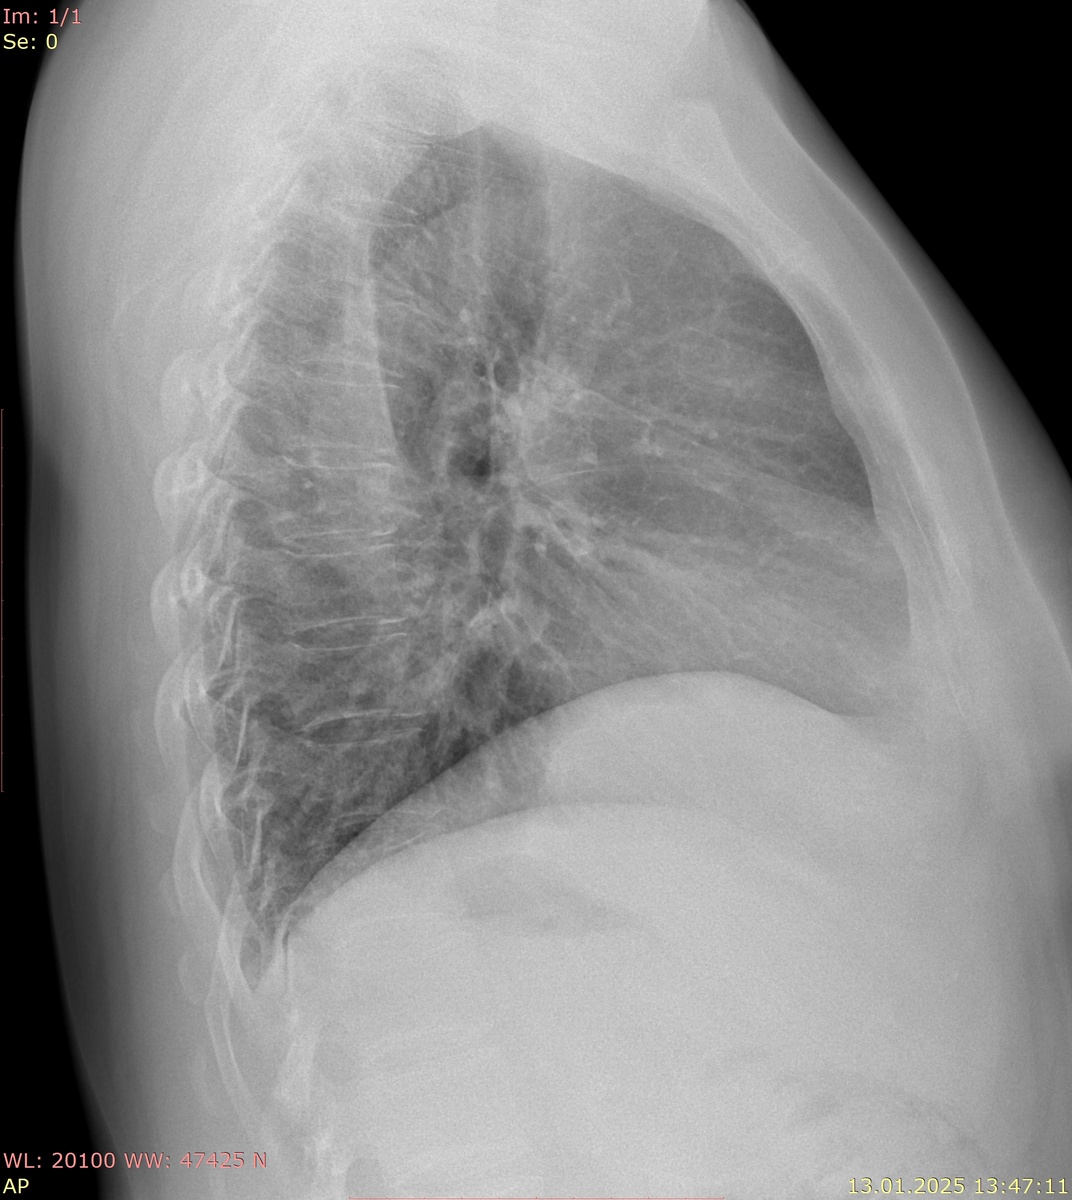

Легочные поля (зеленый - позвоночник) и сердце